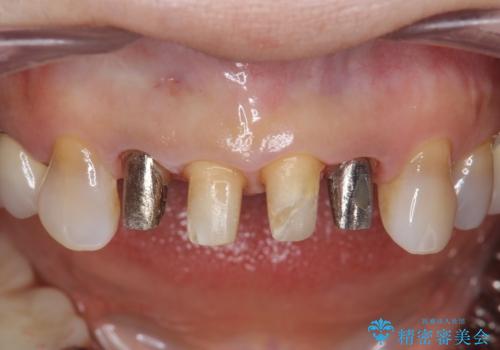

左上の前歯のみねじれが大きいため、歯の位置をひっこめたかぶせものにするために、神経の治療を行っています。

両側の歯の神経の治療および土台のやり替えは行っていません。